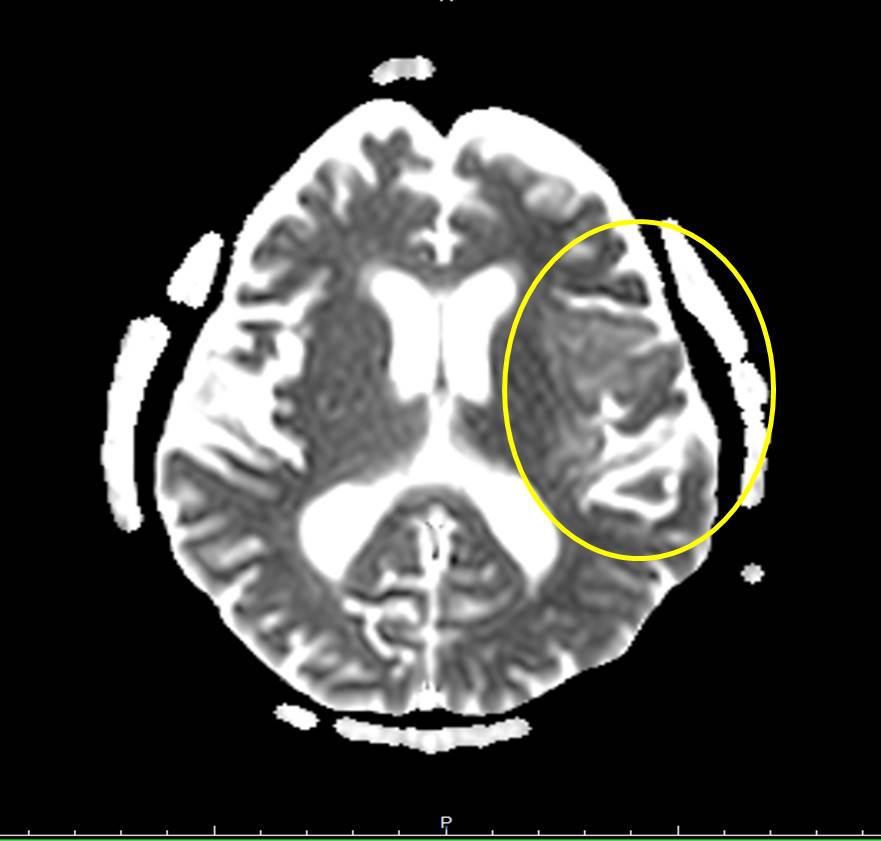

【記者林獻元台中報導】衛生福利部豐原醫院收治一名八十多歲女性,年初曾嘴角長水泡診斷為皰疹感染,同年三月又因臉歪嘴斜、說話口齒不清,至豐原神經外科門診求治,期間一度診斷為暫時性腦缺血,經腦部電腦斷層無特殊異常發現,在藥物治療後症狀緩解,出院後一週病人感覺不適、意識改變、不明原因發生癲癇,立即送醫,收治神經外科加護病房進行插管治療,並安排腦部核磁共振檢查診斷為腦炎及腰椎穿刺檢查採集腦脊髓液送檢驗,檢驗結果為第一型單純皰疹病毒感染,會同感染科主任黃駟榮醫師使用抗病毒藥物治療,治療後病人從意識昏迷、無法溝通,恢復到可以做簡單溝通、恢復狀況良好,讓家人感到欣慰。

豐原醫院感染科主任黃駟榮醫師表示,腦炎病因有病毒、細菌、真菌、寄生蟲等,病毒佔大多數,而單純疱疹病毒又佔了病毒性腦炎的多數,在免疫力較差的情況下,原本發生在身體其他部位的病毒感染,可能經由血液將病毒擴散至腦部而引發腦炎,如治療不及時會造成死亡率高,存活後易有有神經相關後遺症,例如意識不清、癲癇、實質性的腦部損傷等。